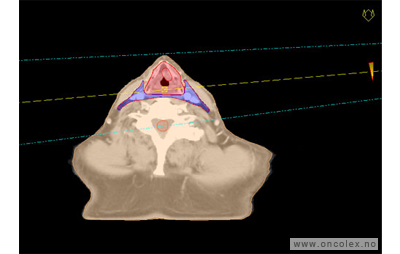

Skisse over hvordan strålefeltet planlegges:

Illustrasjon for målvolum

• GTV (Gross Tumor Volume): Identifisert tumor.

• CTV (Clinical Target Volume) GTV + omkringliggende vev hvor det kan væremikroskopisk spredning.

• ITV (Internal Target Volume): CTV + en indre margin som tar hensyn tilindre bevegelser og endringer av CTV.

• PTV (Planning Target Volume): Innstillingsmargin som inneholder ITV og samtidig tar hensyn til antatte pasientbevegelser, samt variasjoner i pasientopplegging og feltinnstillinger.

• Feltgrense. Tegnes som oftest på kroppen.

ICRU (International Commission on Radiation Units and Measurements)